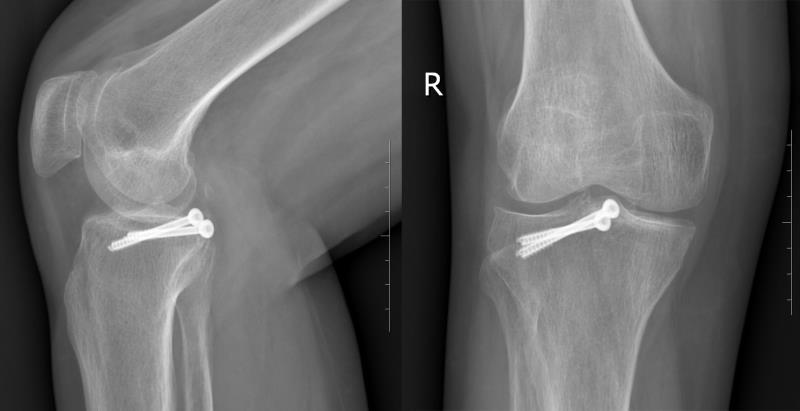

CT提示右膝后交叉韧带胫骨止点撕脱骨折

关节镜下在后交叉韧带胫骨止点撕脱骨折块上植入2枚空心螺钉

术后复查右膝关节CT及三维重建,提示骨折能够达到解剖复位,内固定位置合适

术后3月复查X线片提示骨折达到骨愈合